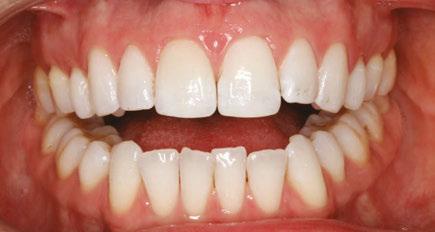

Figures 6 through 9 demonstrate a patient successfully treated with NiTime Aligners following the patient’s rejection of other systems. Figures 6 and 8 display pre- and posttreatment photos of a patient that presented with a Class II malocclusion and normal OB/OJ. This patient has teeth Nos. 7 and 10 missing congenitally. Note that the patient was treated as a child and has a canine substitution due to the missing lateral incisors. Recession was noted on tooth Nos. 2,3, 4, 5, 9, 11, 13, 14, 22, 24, 26, and 27. The patient tried labial and lingual brackets unsuccessfully, as well as a leading clear aligner to correct her malocclusion as an adult. In all three treatments, the patient could not tolerate the mechanics due to increased discomfort and was unable to complete therapy.

It is important to note that there was no refinement required for this case, and the patient finished in 26 weeks with 26 trays. Although the patient presented with significant recession, it did not worsen with treatment. As demonstrated in Figure 9, teeth aligned as planned by the OrthoFX treatment plan shown in Figure 7. Overlays of the actual results with the original treatment plan indicate a high level of predictive accuracy. Not only was a satisfactory result produced from the patient wearing the aligners, but the accuracy is quite high for the NiTime material despite the patient wearing it significantly less than the traditional 22 hours per day.

Figure 6: Class II malocclusion pretreatment

Figure 8: Class II malocclusion posttreatment. Left column pretreatment. Right column posttreatment 22 stages